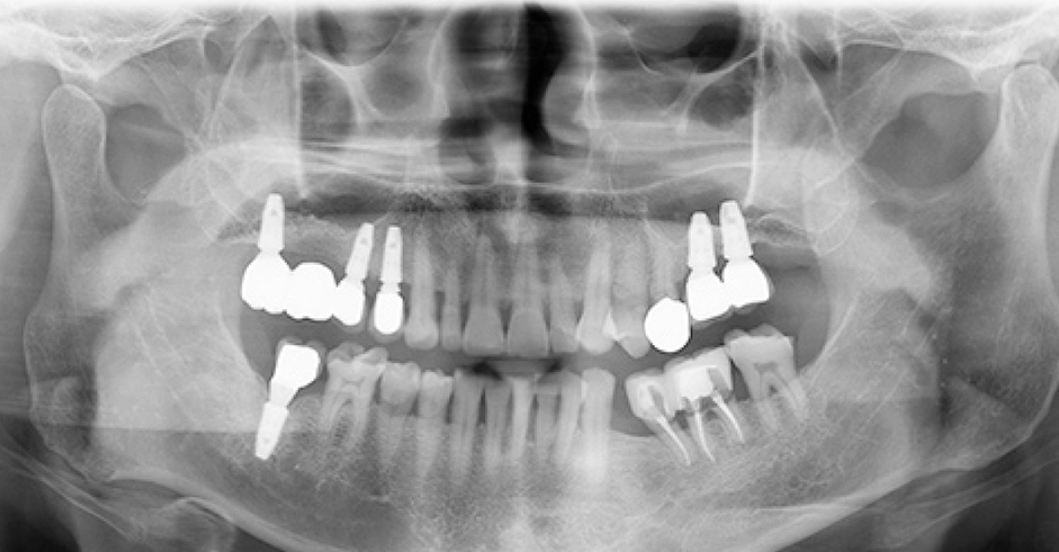

만만치 않은 임플란트 시술 비용 때문에 건강과 행복을 위해 필요한 치료인데도 부담이 되는 것은 사실입니다. 저 또한 고민 중에 있고 만만치 않은 비용과 어느 치과가 임플란트 시술을 잘하는지 잘 모르기 때문에 쉽게 결정을 못 내리고 있습니다. 이러한 어려운 결정에 조금이나마 도움을 드리고자 하여 부산 강서구에서 임플란트 잘하는 곳을 추천 드리고 임플란트 저렴한 치과 가격, 시술 후기를 모아봤습니다.

추천드리는 치과의 규모, 사용하는 재료의 종류, 그리고 환자들의 후기 등을 종합적으로 고려하여 선정되었습니다.